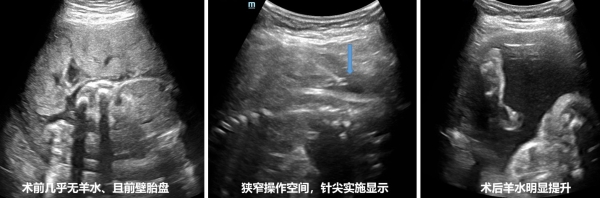

8月3日,一位羊水指数为2.4cm的孕妇入住了产科病房。尽管使用了多种保守疗法补充羊水,仍无明显效果。由于几乎没有羊水,胎儿好像被施了“魔法”,在妈妈子宫里只能保持一个姿势,而且随时有胎死宫内的可能。面对羊水过少可能对孕妇和胎儿造成的不良影响,妇产科副主任段钊迅速组织了包括超声医学科副主任姜珏等多位专家组成的多学科会诊,共同讨论,决定采用超声引导下的羊膜腔灌注术。这一技术能够解决孕妇顽固性羊水过少问题,但对于几乎无羊水孕妇具有较高的技术难度。

手术于8月8日上午顺利进行,在妇产科副主任段钊和超声科副主任姜珏的全程指导下,由余珊珊主任医师和何鑫主治医生为该患者实施超声引导下羊膜腔灌注手术中,术中团队面临以下主要技术难点:1、极窄的操作空间:患者的羊水量极少,前壁胎盘进一步限制了可供操作的空间。穿刺针只能在1cm宽的狭窄羊水间隙中操作,而该间隙因胎儿活动和孕妇呼吸而时有时无,稍有偏差就可能无法准确进入羊膜腔。这要求操作者在瞬息之间精准把握穿刺时机,操作过程中需要高超的手眼协调能力和丰富的临床经验。2、妊娠期子宫肌壁间血管异常丰富增加了穿刺难度。穿刺针不仅要穿越厚实的肌壁,还需避开丰富血管丛,确保进入羊水间隙而不损伤血管。这对操作的精确性提出了极高的要求,稍有不慎可能导致严重出血或其他并发症。3、长时间、高精度操作要求:由于羊水灌注速度受限,每分钟仅能注入3ml,整个治疗过程持续了2小时。在此期间,医务人员需持续监控针尖位置,随时调整穿刺方向,避免因胎儿活动导致针头误伤胎儿或脱出羊膜腔。每一个微小的调整都必须准确无误,以确保灌注过程的顺利进行。4、MDT通力合作:妇产科团队对胎心和宫缩情况进行了密切监控、全操作期管理,确保母婴平安。

经过团队的精准操作和协同配合,操作顺利完成,当500毫升37℃温热的生理盐水进入羊膜腔内后,在超声监测下,清晰地看到胎儿从俯卧位改变为仰卧位,胎儿就像在碧蓝的海水中,终于可以自由的遨游。术后,羊水指数提升到了18CM。听到这个结果后。这位准妈妈开心的说:“医生,通过你们的努力,我的孩子终于自由了,谢谢你们。”